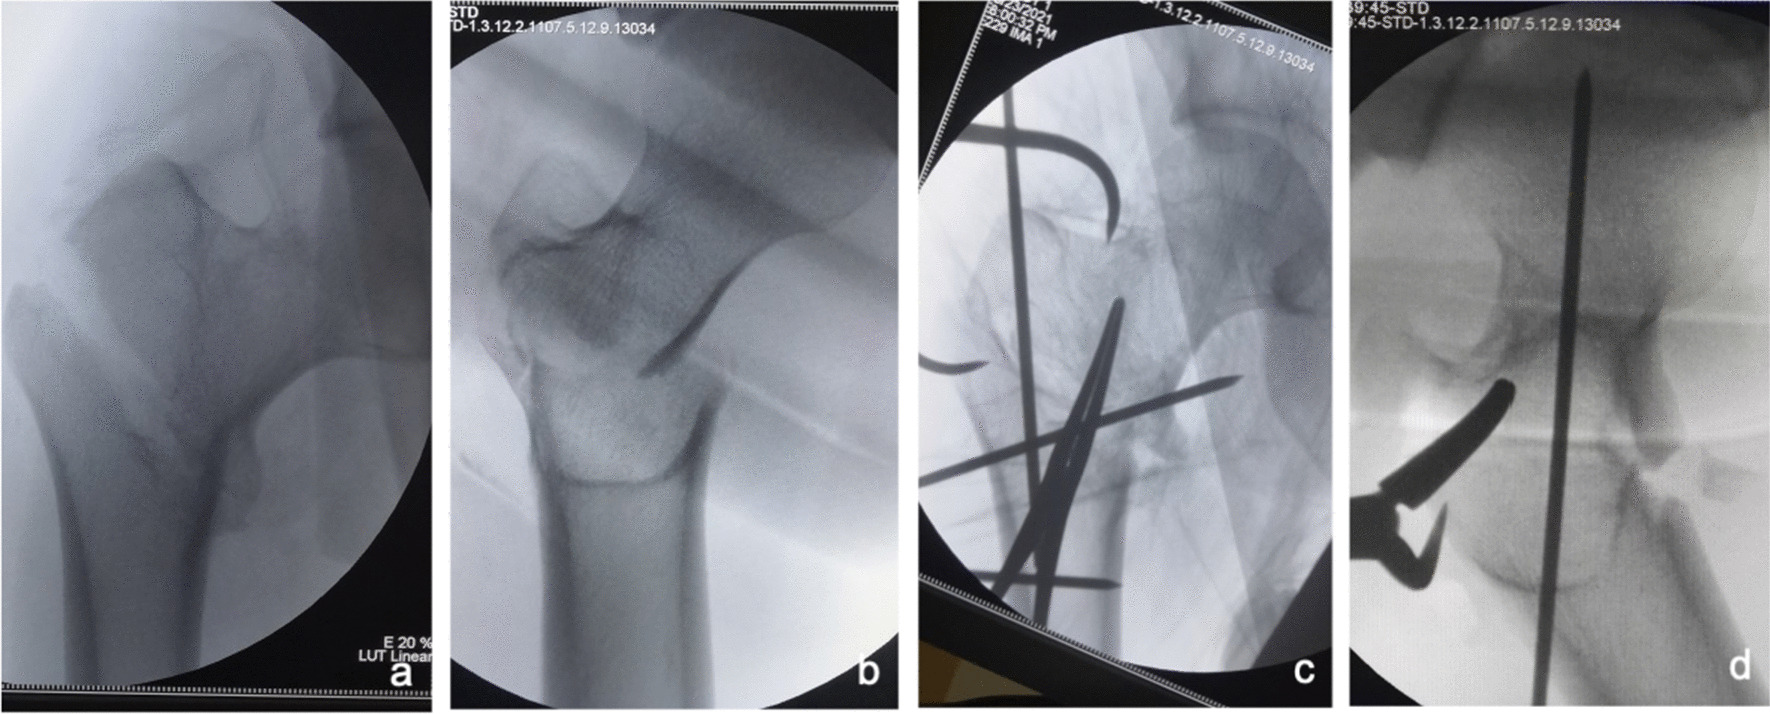

Fig. 9.

Anteroposterior and lateral X-ray films before and after reduction in patients with difficulty in reduction on both sagittal and coronal planes and supination and internal rotation or external rotation displacement of the proximal fracture segment a, b Before reduction; c, d After reduction